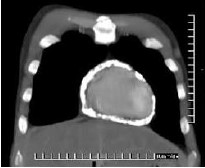

A tomografia computadorizada de tórax de um paciente apresentou a seguinte alteração:

As opções a seguir apresentam achados característicos do seu exame físico cardiológico, à exceção de uma. Assinale-a.